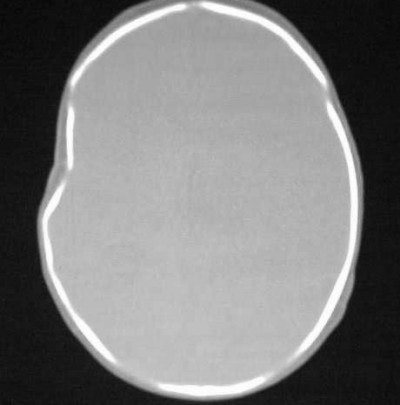

How about CT imaging for an in vitro trauma? Figure CT 5 is an axial image of a newborn child; there were no problems during the caesarian delivery. Two physicians and three nurses were present and the child was noted to have an indentation to the temporal region of the skull. Plain films were positive for a depressed skull fracture (Figure CT 6).

![]() |

| Figure CT 5 |

| Figure CT 6 |

Three-dimensional reconstructed images in surface-shaded volume rendering show an obvious breech of the skull in the affected area (figures CT 7 and CT 8). Detectives matched the defect to a pair of the father’s cowboy boots. He was charged and convicted of beating his wife during the pregnancy.